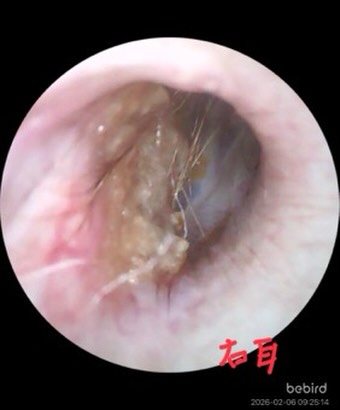

歯周疾患診療

人と同じように犬猫も口腔内環境が重要です。